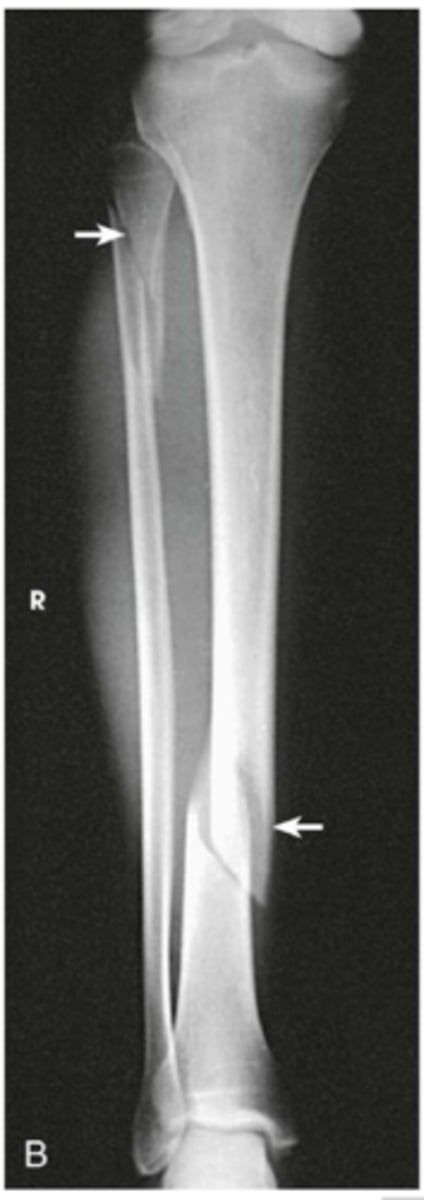

How do we get best imaging of a fracture

Xray assessment

What is an open/compound fracture

- skin break

- fracture is piercing skin, exposing bone

What are the types of unstable fractures

- oblique

- spiral

- comminuted (fragmented/cracked & compressed bone)